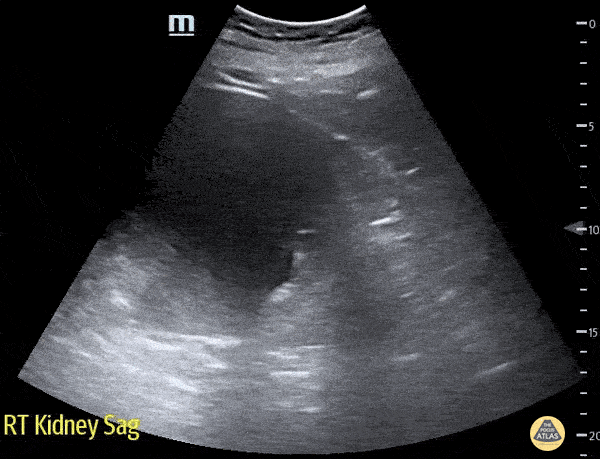

83 year old male presented to the ED for right flank pain. The renal ultrasound showed two right renal cysts. The superior renal pole cyst measuring 12 x 13cm. The inferior pole cyst measuring 4 x 5cm. Laura Schroeder, MS, MD; Syeda Zehra, MD; Conner Shea (Medical Student) Central Michigan University Emergency Medicine Residency